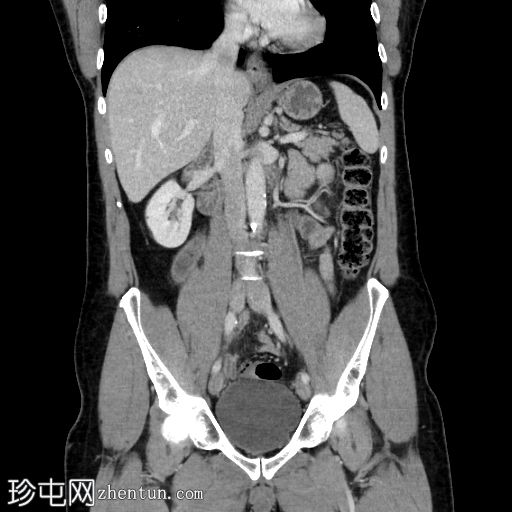

CT

冠状位增强扫描(门静脉期)

阑尾扩张、增厚、强化,可见少量管腔外气体。右下腹及盆腔可见无序液体(伴有少量下垂钙化灶)及条索状改变。未见其他急性期征象。

本病例是阑尾炎早期穿孔的典型病例,仅可见少量管腔外气体,初次检查可能难以发现,且盆腔积液量较预期。盆腔内少量分层钙化灶可能是游离阑尾粪石,也可能是慢

性病

变(例如既往大网膜垂扭转所致)。